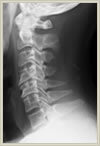

頚椎は7つの椎骨で構成されており、椎骨の後方には腰椎と同じく脊柱管という神経の通り道が存在します。頸椎の場合は腰椎と異なり、脊柱管の中を通っている神経は脊髄と呼ばれ、脳と同じ中枢神経です。このため、腰椎と同様の圧迫性病変でも異なった症状を呈します。頚椎症性脊髄症とは頚の椎骨(頚椎)に加齢性変化が生じ(頚椎症)、これにより脊髄の症状(脊髄症)を生ずるという意味です。頚椎椎間板ヘルニアは腰椎椎間板ヘルニアと同じ病態ですが、症状が頸椎部と腰椎部では違ってきます。頚椎部の場合は椎間板ヘルニアの場所によっても違いますが、頚から上肢にかけての放散痛(電気が走るような痛み)が典型的で、これは頚を動かすと増強します。また中心部に突出すると頚椎症性脊髄症と同じく脊髄の症状を呈します。脊髄の症状というのは具体的には、手の細かな運動が困難(お箸が持ちにくい、字が書きにくい、ボタンがはめにくい等)になったり、脚が突っ張って歩きにくい、階段を下りるとき足ががくがくする、上肢の筋萎縮、脱力、上下肢および体幹のしびれなど、全身に症状が出現します。頚椎椎間板ヘルニアの放散痛であれば、保存的加療(投薬、安静、リハビリテーション、注射など)で症状が軽減する場合が多いですが、脊髄の症状の場合は徐々に進行する場合が多く、症状の程度により手術が必要になる場合もあります。手術は後方法と前方法の2種類がありますが、それぞれ一長一短があり、画像所見や臨床症状によってどちらを選択するか決めています。 1ヶ所の頚椎椎間板ヘルニアで後方から摘出可能なケースでは、腰椎椎間板ヘルニアと同じく、直径18ミリの内視鏡チューブを用いて手術を行っており、2センチの傷ですみ、入院期間も約7日間となります。